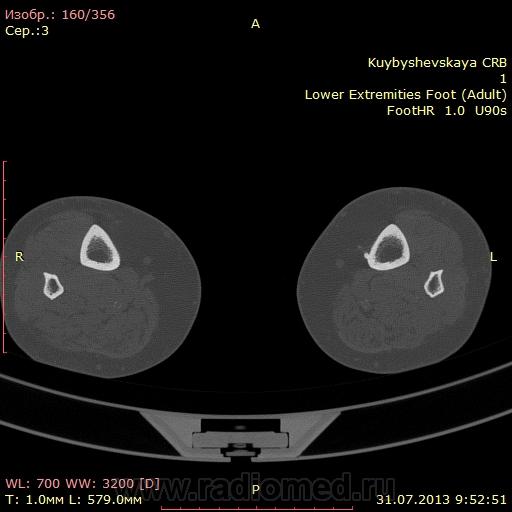

женщина. 69 лет. жалобы на боли в нижней трети голени слева в течении месяца. по снимкам врач написал периостит(к сожалению фотоаппарата нет под рукой)В ближайшее время травм не было. мне досталась только карточка. Пациента не видел. Помогите с диагностикой. вроде бы на зло не похоже. или ошибаюсь?

На зло непохоже, нет мягкоткотканного компонета. Передне-медиальная поверхность голени - самое место для травмы. Только термин "периостит" мне тоже не нравится, написал бы - локальное обызвествления мягких тканей, вероятнее всего посттравматического характера.

По снимкам описал бы как обызвествившуюся гематому, а по КТ больше тянет на экзостоз, только основание очень широкое.

Тем более не "зло". На боковом снимке, в захваченной стопе, р-признаки синдрома переднего большеберцово-таранного соударения. Она же стопа "футболиста" или спортсмена

Может "...в ближайшее время травм И не было...", но что его, наверняка, когда-то "подковывали" бутсой по передней поверхности голени, несомненно.